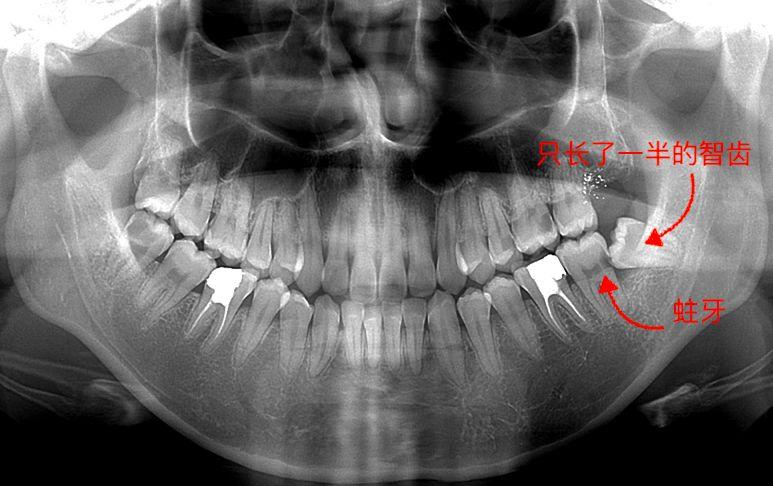

圖一,手指的這顆,很比別的牙矮,沒(méi)有長(zhǎng)出來(lái)是埋伏型的一顆,為什么去拔,因?yàn)樗鋵?shí)有頂我旁邊牙齒了,影響我這邊吃東西了,咬東西隱隱作痛,而且只要人不舒服這邊準(zhǔn)發(fā)炎和牙齦紅腫。

牙片,手指著的就是有問(wèn)題的智齒

▼